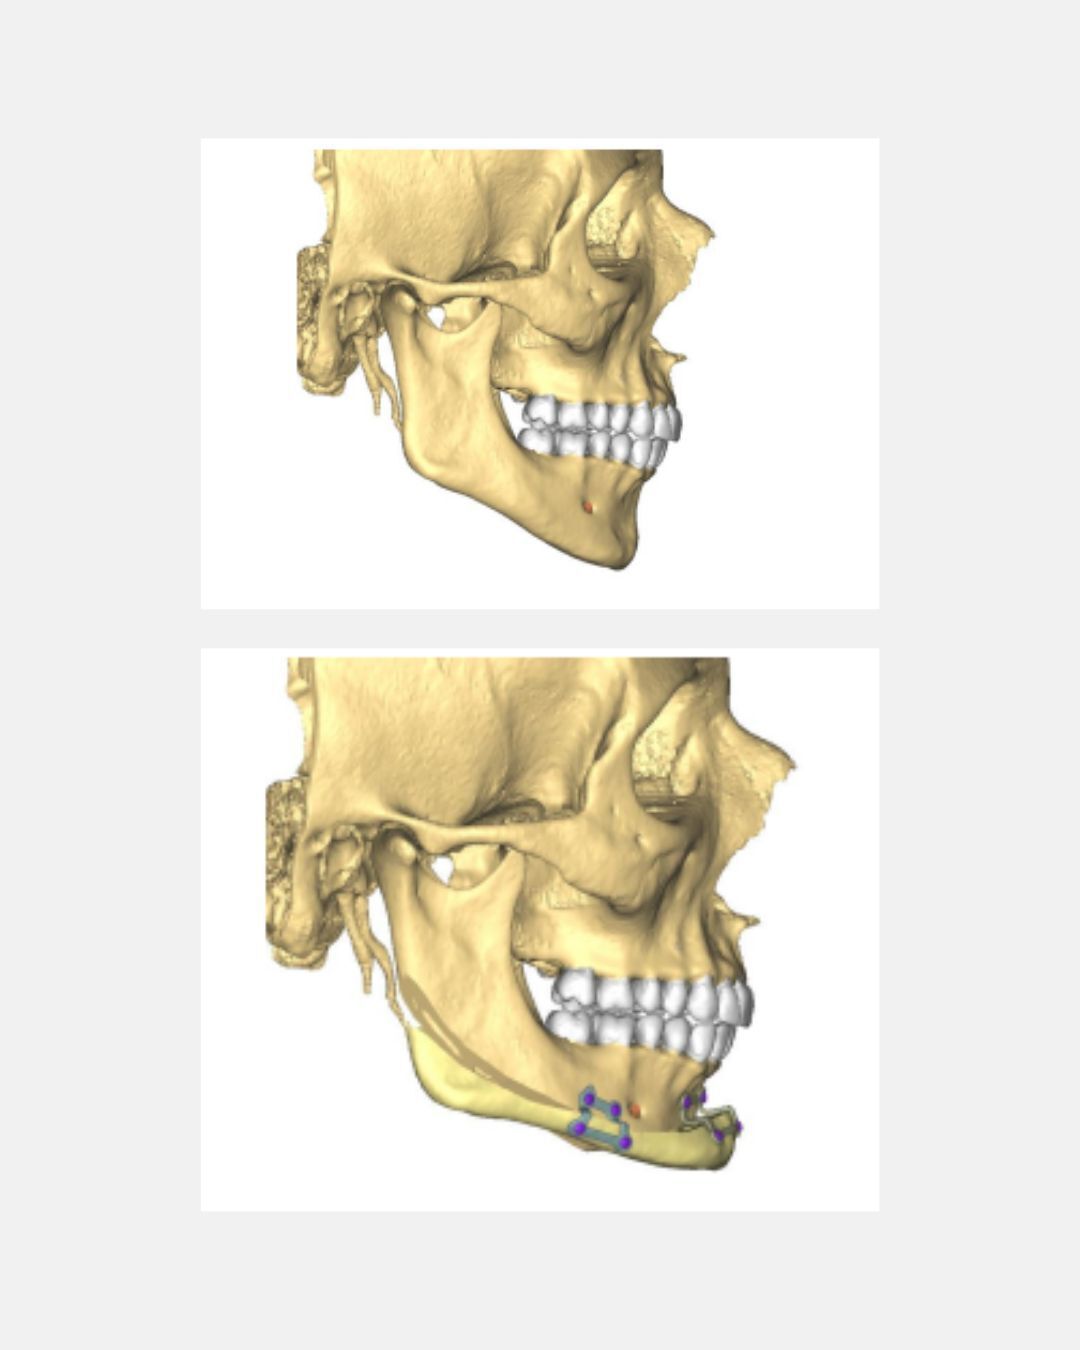

Knowing chin wings can perform such cuts :

... why not going for a cut like below to fix so-called "inward gonions" ? You can then imagine a variety of movements and segmentations to attain the desired result, akin to chin osteotomy.

Knowing chin wings can perform such cuts :

... why not going for a cut like below to fix so-called "inward gonions" ? You can then imagine a variety of movements and segmentations to attain the desired result, akin to chin osteotomy.